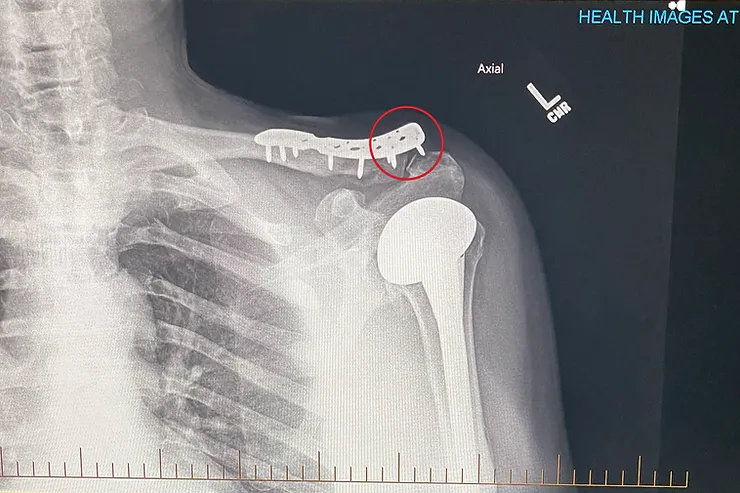

There was a complication, though, of the addition of a broken collarbone and the plate that it had

required. My doctor had assured me that I could "leave it in". But it took just a few days of riding longer distances for it to be clear that wouldn't be the case. Spiz freaked out when he saw the plate sticking up from my shoulder. I started to get this crazy bruising and, the more I rode, the bigger the bruise became. I went back to my orthopedist who told me "I think it'll be fine." It didn't feel fine, and it didn't look fine. It was creepy. I scheduled an appointment for him to remove the plate. 6 Months after—Setback Number Two Plot twist. My doctor acquiesced on removing the plate, but when I went back for my check up for THAT surgery, Donna and I could immediately see on the x-ray, before the doctor even came back into the room, that there was a screw still in there.

Again, he encouraged me to leave it in/live with it. After everything, I hated knowing it was there. And my physical therapists were scaring the shit out of me, "we don't want the liability of that screw moving down in your joint." And they said I shouldn't ride either. I can now say I'm happily devoid of all extra hardware, but the time it took to resolve both issues pushed my physical therapy back by several weeks, if not months, impacted my cycling, and messed with my head the entire rest of the year. While it wasn't all bad. It wasn't that good either.